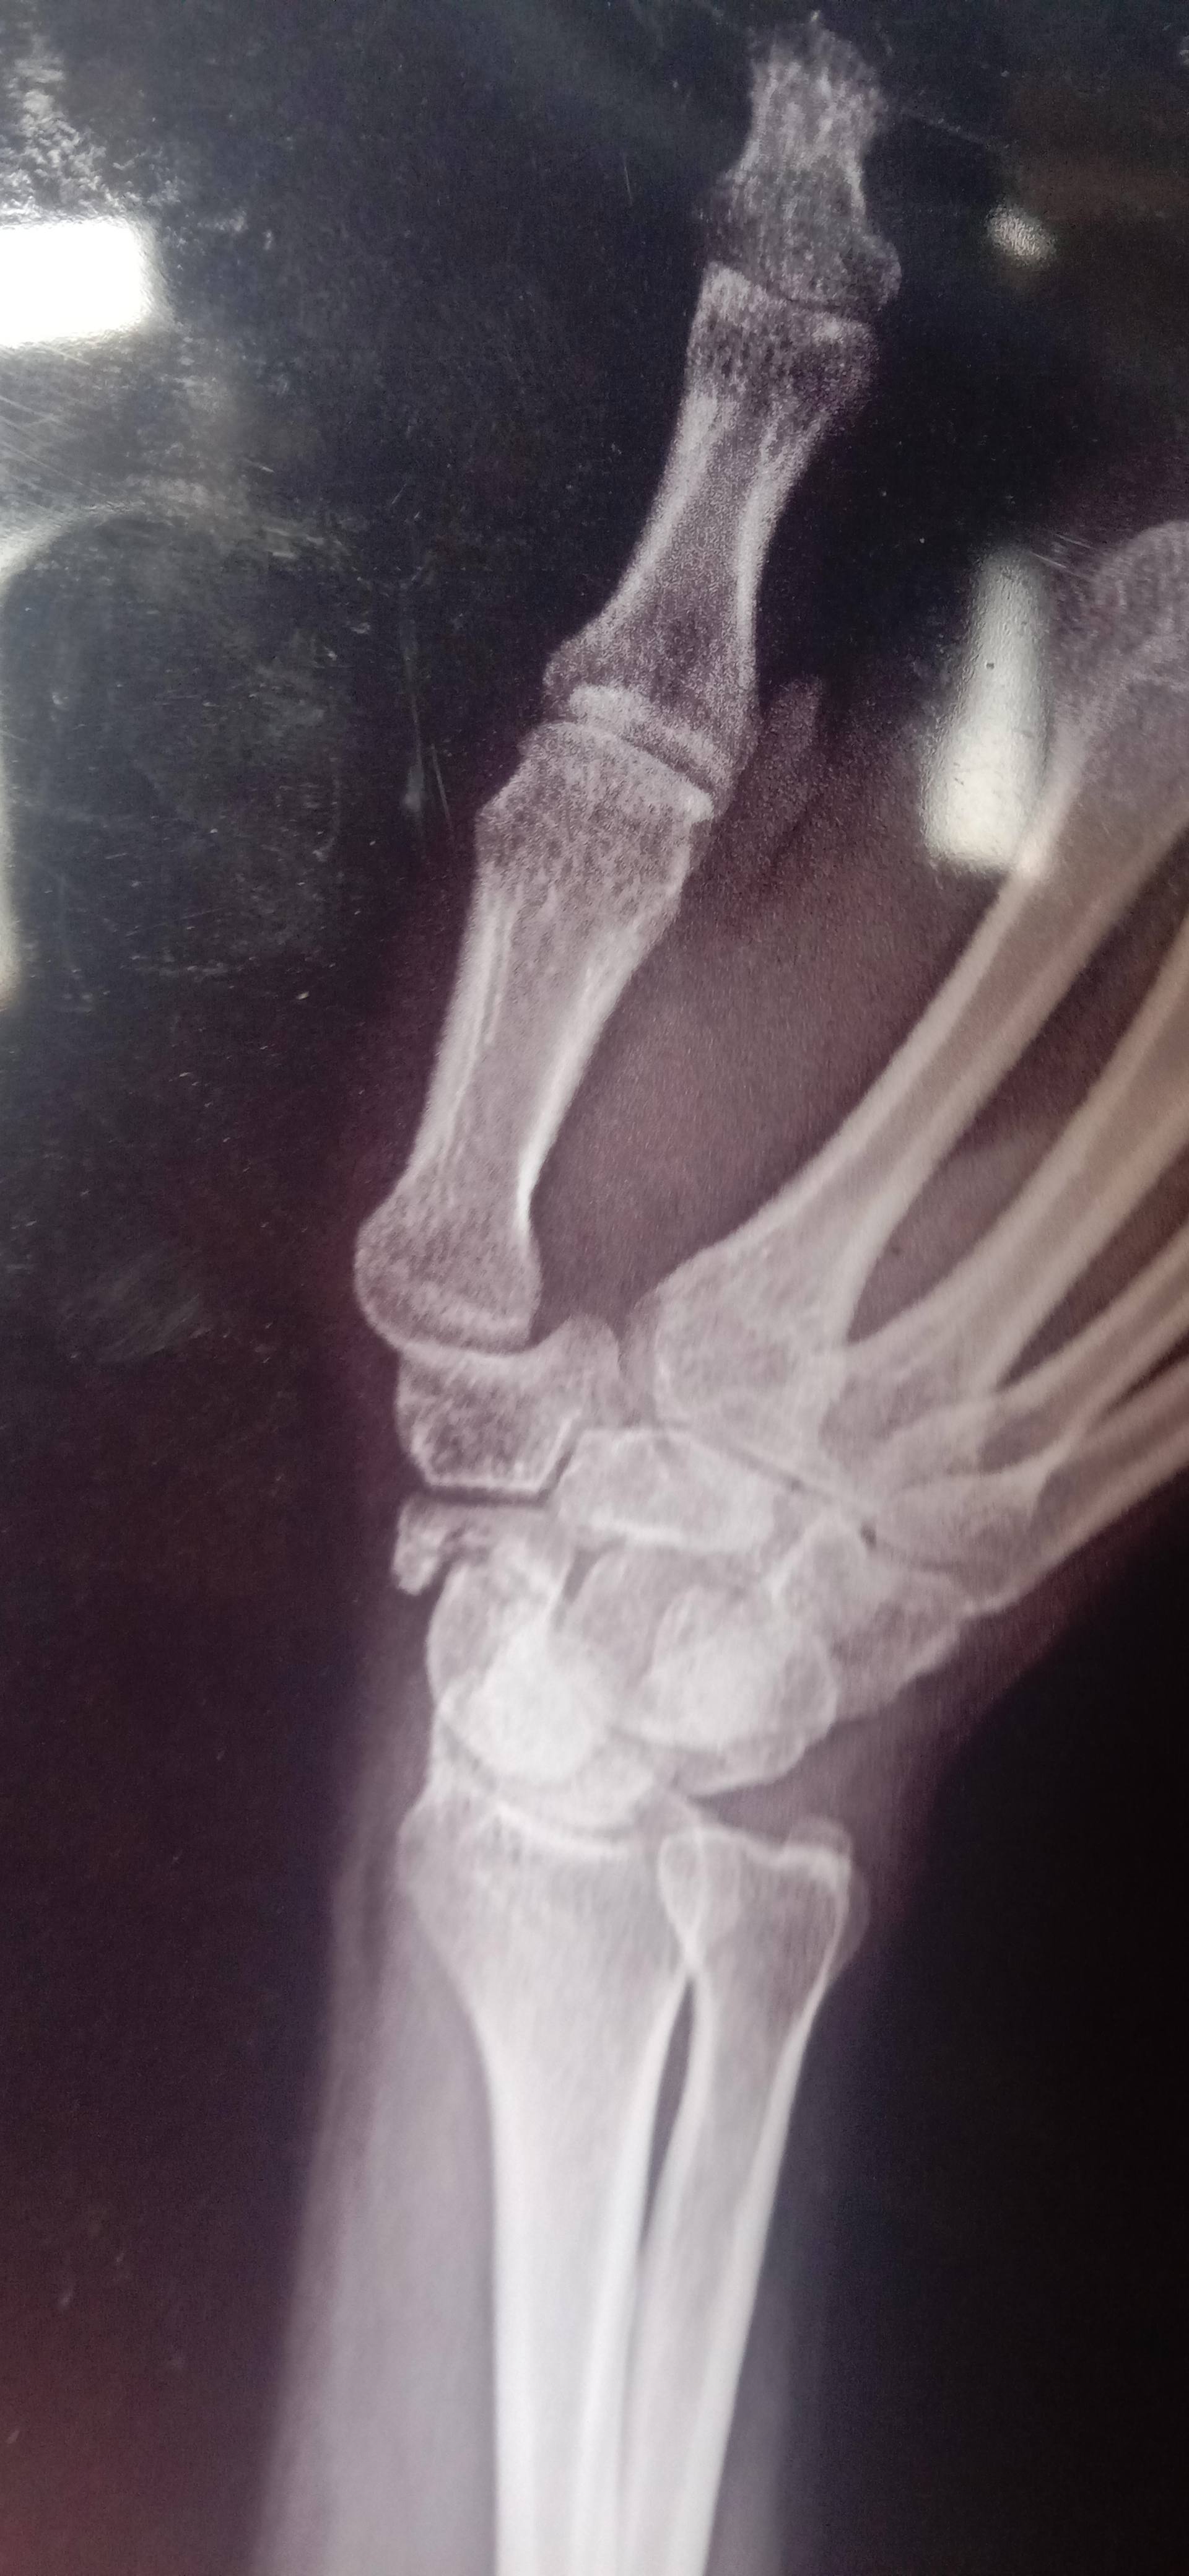

sir mara scaphoid ka fracture ha

Sir 4 months

Isme kitna time ho gaya hai .